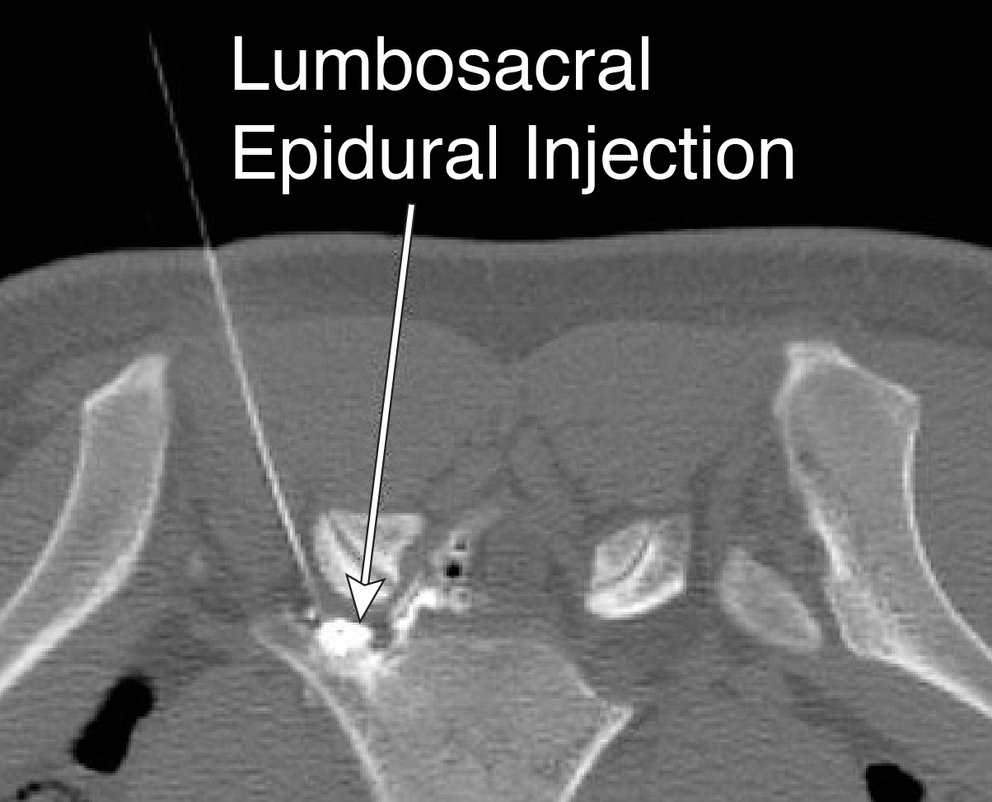

Epidural Injection Procedure Epidural Steroid Injection How Long To Take Effect But sometimes, it can take up to a week to. A doctor will inject steroids into. an epidural steroid injection is a nonsurgical procedure that provides pain relief. While evidence shows that epidural steroid injections are effective in providing pain relief, the length of. Epidural steroid injections can help resolve pain permanently in patients with a new disc herniation.. Epidural Steroid Injection How Long To Take Effect.